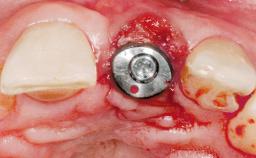

A 36-year-old female patient was referred for the replacement of the upper left central incisor (tooth 21), which had fractured. Although the tooth had been asymptomatic for many years, the crown began to loosen, at which time she presented to her dentist for an assessment. Teeth 21 and 22 had both been endodontically treated many years previously. She was a healthy individual and a non-smoker.

- Surgical SAC classification

- Complex

- Prosthodontic SAC classification

- Advanced